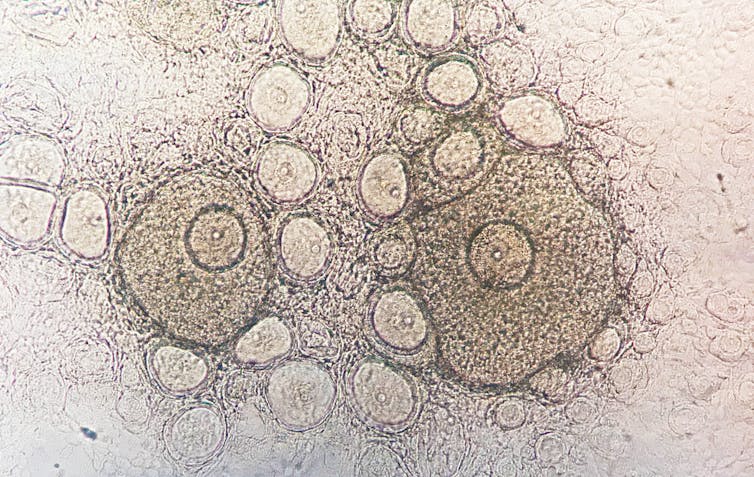

Eso sí, la mayor parte de estas investigaciones sobre disruptores se han llevado a cabo en el sexo masculino. Porque es más fácil obtener los espermatozoides y por la tremenda complejidad biológica de la diferenciación de los ovocitos durante el desarrollo femenino. Últimamente hemos empezado a ponerle remedio. Desde nuestro laboratorio y desde otros muchos se han puesto en marcha estudios en modelos animales usando métodos de cultivo in vitro de ovario desde etapas embrionarias del desarrollo.